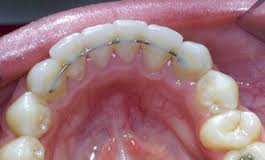

Každá ortodontická vada má přirozenou tendenci vracet se do původní pozice, tedy recidivovat. K zabránění recidiv je nutno nosit po léčbě sundávací rovnátko (retenční deska nebo fóliová dlaha) k udržení stavu vyrovnaných zubů. Tato retenční zařízení se nosí první měsíce po sejmutí fixního aparátu intenzivně (16 hodin denně), poté intenzita nošení postupně klesá. Zároveň po léčbě podlepujeme přední zuby ze zadní strany tenkým drátkem ( fixní retainer), který má také za úkol zuby po léčbě udržet v požadované pozici.